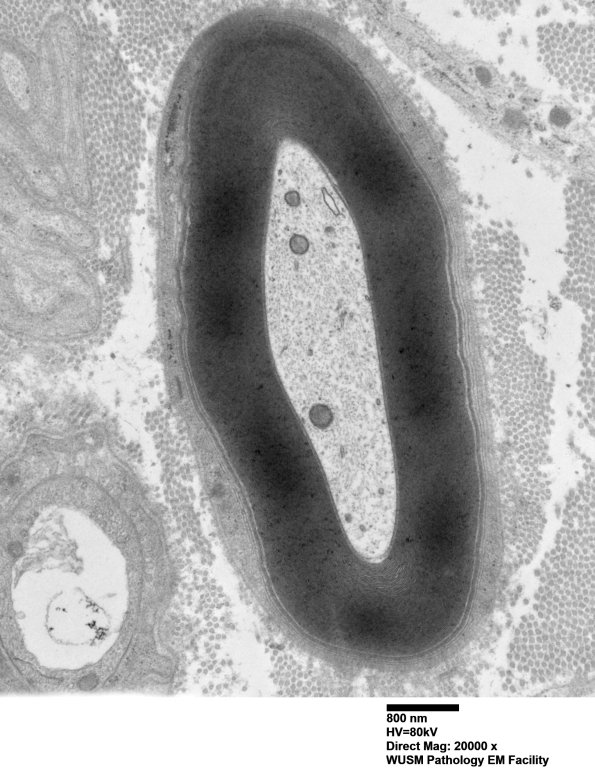

By itself this axon would not be compelling for the diagnosis of anti-MAG neuropathy. The diagnosis made was “suspicious for anti-MAG neuropathy”. (electron micrograph)